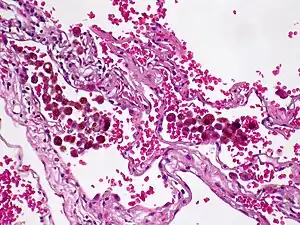

Hemossiderose é uma doença caracterizada por depósitos anormais de hemoglobina, geralmente nos pulmões (hemossiderose pulmonar) ou no sistema nervoso (hemossiderose superficial).

Vários episódios de hemorragia nos alvéolos dos pulmões levam à uma acumulação anormal de ferro como hemossiderina(proteína que transporta ferro orgânico) dentro das células responsáveis pela limpeza (macrófagos) e ao desenvolvimento de fibrose pulmonar (cicatrizes pulmonares) e anemia ferropriva (poucos glóbulos vermelhos). [1]